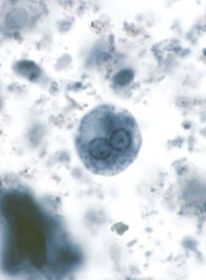

BALANTIDIUM COLI Tsüst Äigepreparaat parasiidi kultuurist